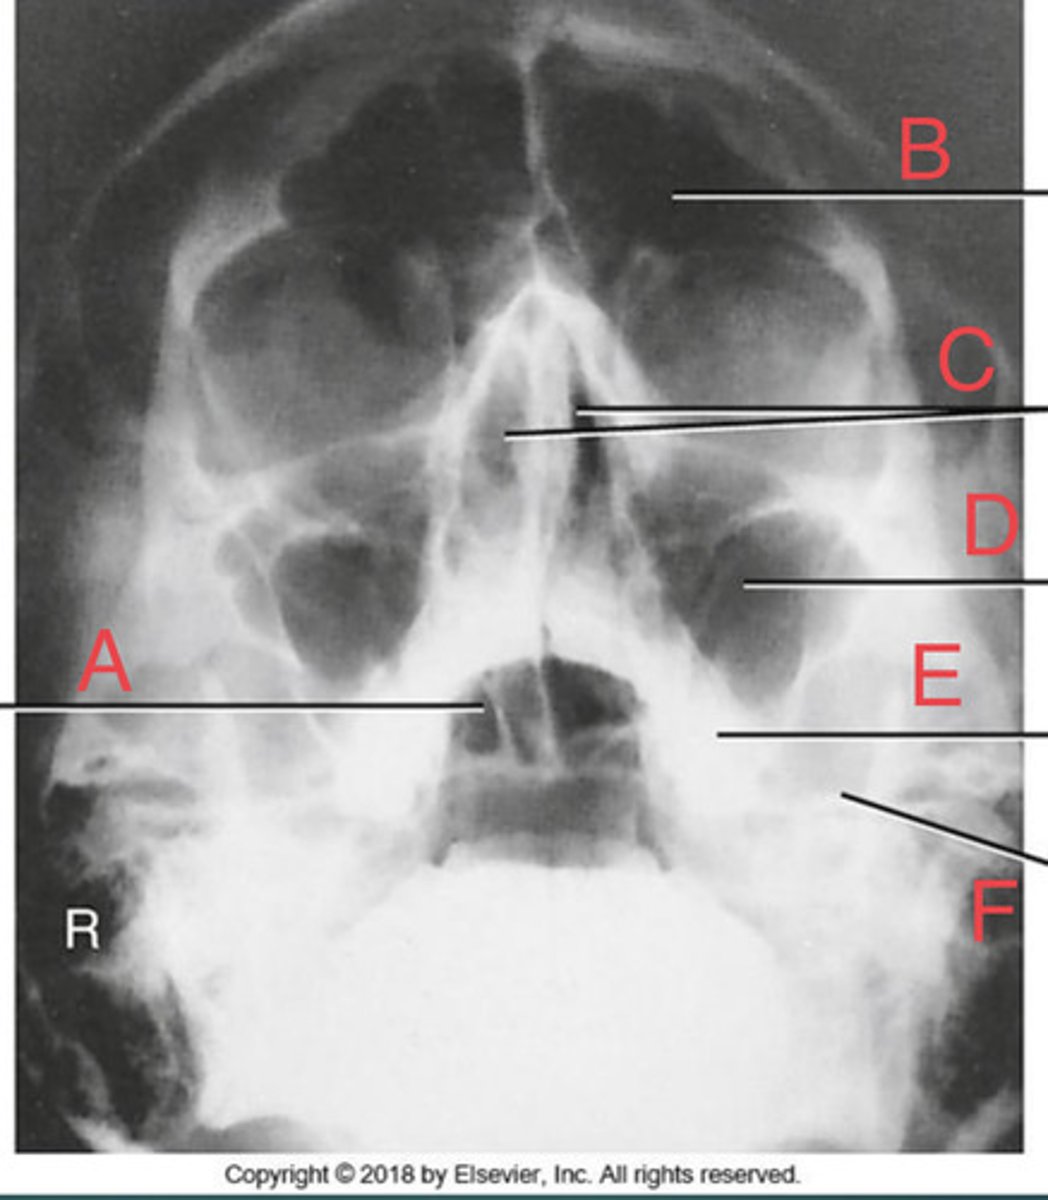

Waters sinus method

What projection?

r. frontal sinus of the frontal bone

A.

R. Maxillary sinus of maxilla

B.

R. petrous ridge of temporal bone

C.

bony nasal septum

D.

L. inferior orbital fissure of sphenoid bone

E.

Sphenoid sinus of sphenoid bone

F.

bony nasal septum

E.